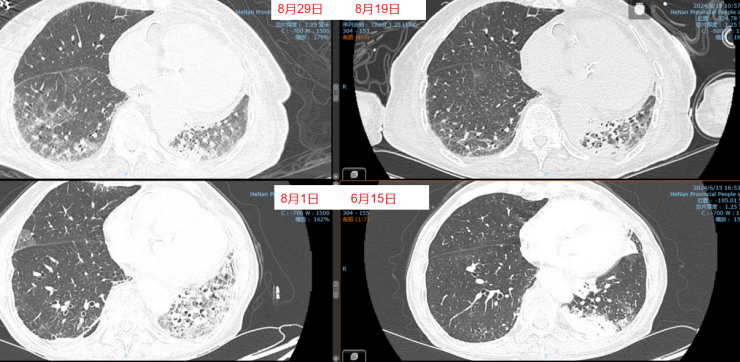

- 胸部CT(2024-06-13):左肺舌段和左下叶斑片实变影,右肺下叶可见斑片状阴影,肺中叶散在病变(图1)。

经过上述治疗,患者WBC、CRP、LDH、PCT均逐渐下降,肌酐正常。8月10日检查:WBC 9.1×109/L,CRP 6.8 mg/L,PCT 0.04 ng/ml,LDH 406 U/L。8月3-10日期间,患者心率持续变快,需要两种血管活性药物控制血压,无法进行俯卧位通气。ECMO上机前,患者右肺渗出性病变明显加重(图3)。

8月11日呼吸机吸氧浓度40%,ECMO气浓度约为80%,持续3天,激素减量氧合恶化,因心脏问题不能俯卧位通气(心率快,应用艾司洛尔及胺碘酮控制心室率)。气道分泌物不多,炎症指标正常。心脏问题,快速性心律失常,请心内科专家会诊,考虑舒张功能障碍,建议盐酸地尔硫卓联合胺碘酮控制心室率,血压低考虑可能血管张力问题,为减轻去甲肾上腺素对心脏的刺激,调整间羟胺维持血压。6月26日用抗肿瘤靶向药物后,8月1日肺部CT,双肺病变明显加重,肿瘤进展还是感染诱发?或是肿瘤靶向药物引起的免疫相关性肺损伤?下一步怎么办?肿瘤靶向药物还能用吗?8月11日请詹庆元教授会诊,考虑肿瘤靶向药物引起间质性肺炎可能性大,甲强龙80 mg q12h;心内科建议倍他乐克6.25 mg q12h口服联合盐酸地尔硫卓控制心室率;间羟胺替换去甲肾上腺素。8月12日心率65~85次/分,俯卧位8小时,白天ECMO 80%下调60%。患者氧合持续好转,随着病情好转,抗生素降阶梯治疗。8月13日,BALF涂片发现大量白细胞,以及多种形态阴性杆菌,像洋葱伯克霍尔德菌和伊丽莎白菌。8月14日,tNGS结果回报按蚊伊丽莎白菌、洋葱伯克霍尔德菌和脓肿分枝杆菌。据此调整抗感染药物:磺胺2片tid,多黏菌素E,美罗培南,利奈唑胺,伏立康唑。8月20日撤离ECMO。8月21日,病原学提示脓肿分枝杆菌进行性增多,加用左氧氟沙星。8月26-28日尝试甲强龙减量(60 mg→40 mg),患者再次再次出现氧合变化,未能成功转换为无创通气,有创通气PS降至8 cmH2O,PEEP 5 cmH2O。复查胸部CT,发现右肺渗出性病变再次出现。8月29-30日,甲强龙剂量调整为80 mg。8月31至9月3日,甲强龙剂量调整为60 mg。8月27日复测tNGS,回报木糖氧化无色杆菌(序列数47605),人类疱疹病毒1型(序列数176998),按蚊伊丽莎白菌、洋葱伯克霍尔德菌和脓肿分枝杆菌序列数较前减少。细菌室回报木糖氧化无色杆菌。患者出现了一些不良反应,包括骨髓抑制,纤维蛋白原、血小板、血红蛋白、白细胞、淋巴细胞数都在降低。考虑可能是磺胺药物和利奈唑胺引起,所以停用这两种药物。调整抗感染药物:阿米卡星雾化,左氧氟沙星,多西环素,伏立康唑,阿昔洛韦。之后由于不良反应,8月31日停用了左氧氟沙星和多西环素。9月3日查血,患者血小板升高。如下图所示,6月15日为抗肿瘤药物使用前,8月1日为抗肿瘤药物使用后,8月19日第一次复查CT,激素减量后,8月29日再次复查CT,右肺渗出性病变较前明显增多(图4)。

图4 患者影像学变化